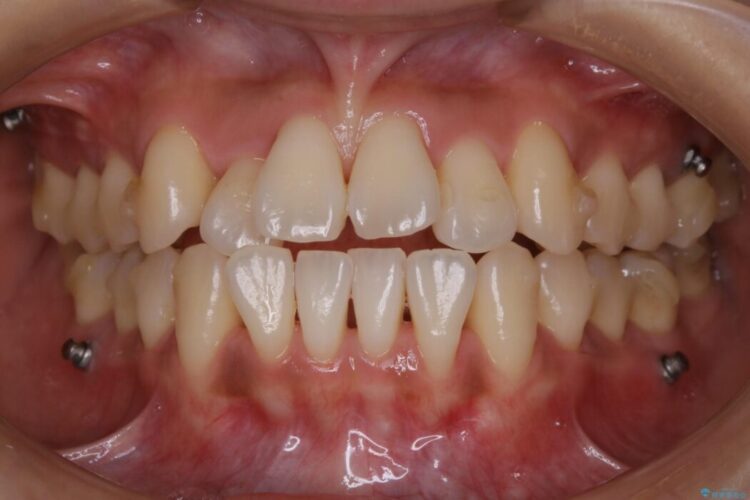

- 患者様:20代女性

- 治療期間:2年

- 矯正装置:インビザライン

- 概算治療費:88万円+TAX(マイクロインプラント費用込)

よってマイクロインプラントを用い、奥歯から順番に遠心移動させることによってスペースを確保することにしました。

歯を後方に移動させてスペースを確保する場合、マウスピースの装着時間に加えて装着時の適合度が良い状態に保たれているかが鍵となります。

歯は戻ろうとする力が強いためマウスピースの装着をしっかりしていただけなかった場合は、作り直しや治療の長期化につながってしまう可能性があります。